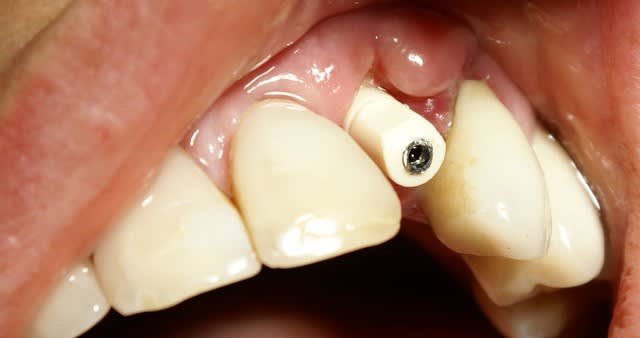

Situation semblable.

Jeune homme, 20 ans, accident de vélo.

Perte de 11 et 21.

Arrive dans mon cabinet 8 jours post trauma.

J'ai placer sous antibio et 2 jours après j'ai curetté les alvéoles, fait lambeau (perte de paroie buccale), placer 2 4,6 X 15 mm en palatin, greffe MINEROS, membranne (suturée sous le lambeau palatin + 2 tacs en titane au buccal).

Extension du lambeau au buccal et fermeture.

Ah oui, freinectomie laser en mêm temps, histoire de s'occuper un peu. Pas de temporisation sur implants avec une perte d'os au buccal. Prothèse acrylique amovible de transition, placée 7 jours post-op.

La 2e photo est 7 jours post-op, la sem dernière.

Zéro enflure, zéro douleur, pas d'anelgésique.